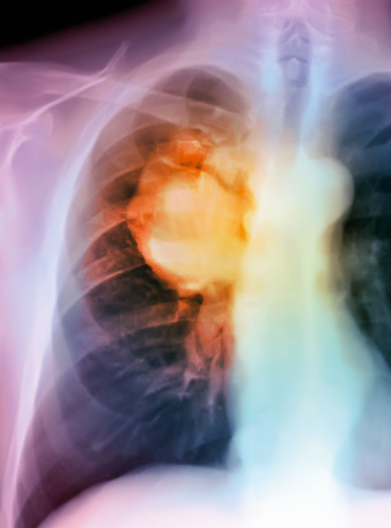

Lung Cancer

The main cause of lung cancer is cigarette smoke. Several studies indicate that there is a clear dose-effect relationship between inhaling tobacco and development of lung cancer.